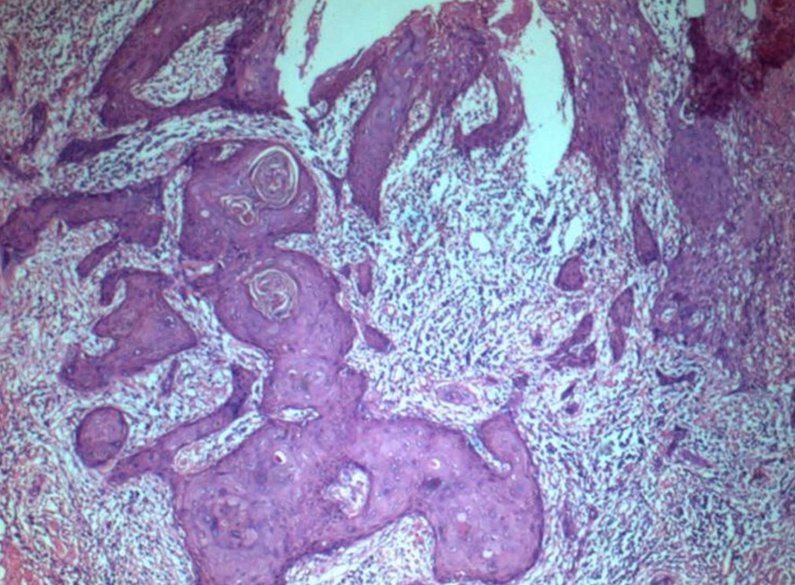

I fattori di rischio del carcinoma orale sono il fumo (20 sigarette al giorno quintuplicano il rischio), l’abuso di bevande alcoliche, un’alimentazione povera di frutta e verdura, l’infezione da papilloma virus umano, l’esposizione ai raggi ultravioletti, per quanto concerne quello del labbro. Spesso la patologia è preceduta da lesioni precancerose della mucosa orale (leucoplachie, eritroplachie), che richiedono una particolare attenzione da parte del paziente e dell’operatore sanitario.